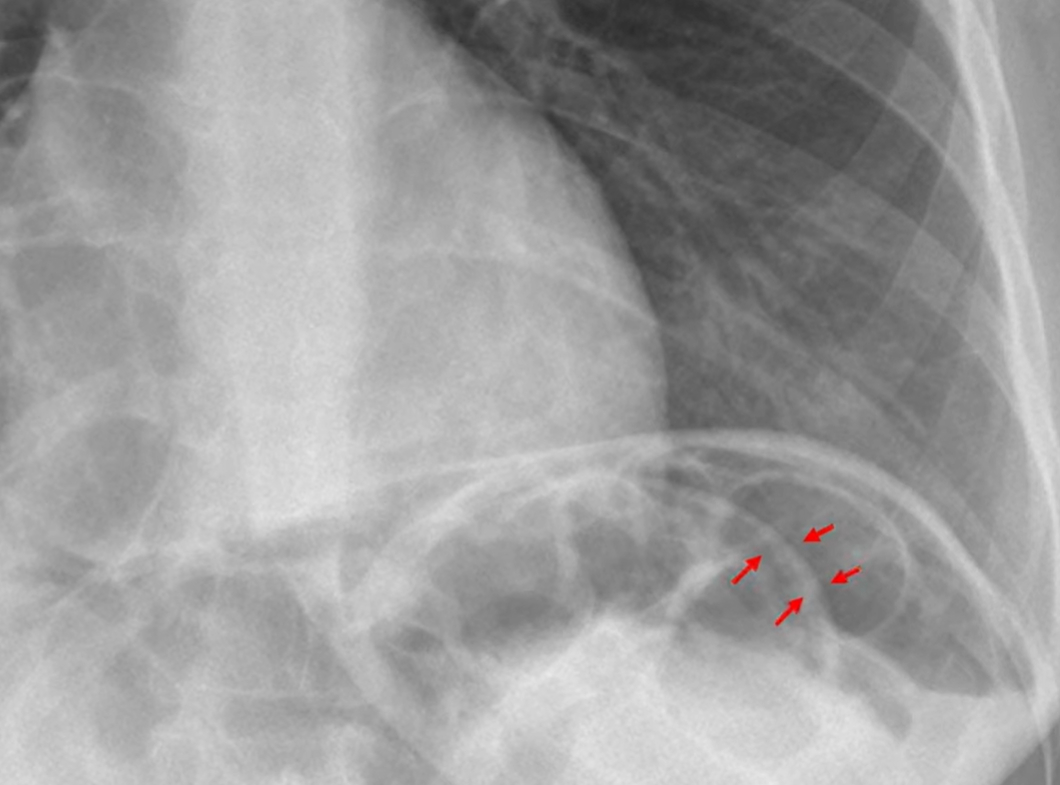

To what structure are the arrows pointing?

A) Inner layers of the intestine

B) Inner and outer layers of the intestine

C) The caecum

D) Outer layers of the intestine

Correct Answer: